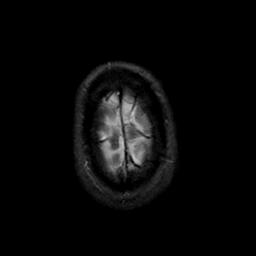

MR Study #23, January 26, 1992 -- Slice #46

[Home][Help][Clinical][Tour 1][Tour 2] Slice 46